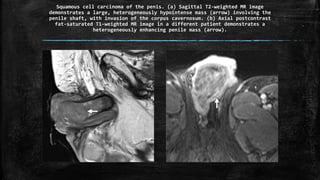

Squamous cell carcinoma of the penis. (a) Sagittal T2-weighted MR image

demonstrates a large, heterogeneously hypointense mass (arrow) involving the

penile shaft, with invasion of the corpus cavernosum. (b) Axial postcontrast

fat-saturated T1-weighted MR image in a different patient demonstrates a

heterogeneously enhancing penile mass (arrow).

Squamous cell carcinomaof the penis. (a) Sagittal T2-weighted MR image demonstrates a large, heterogeneously hypointense mass (arrow) involving the penile shaft, with invasion of the corpus cavernosum. (b) Axial postcontrast fat-saturated T1-weighted MR image in a different patient demonstrates a heterogeneously enhancing penile mass (arrow).